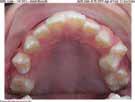

Mahaffey Linkous Orthodontics offers braces and lnvisalign® in conjunction with modern techniques to conveniently uncover your best smile. Dr. Michael Mahaffey, Dr. Eric Linkous, and their caring team of tooth-moving experts make having orthodontic treatment an awesome experience! Schedule your complimentary consultation today to begin your journey to a healthier, more confident smile.